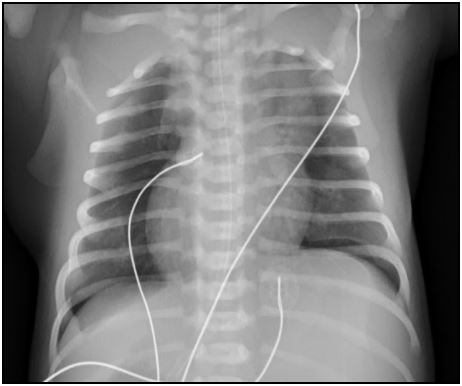

Radiografia De Tórax No Recém-nascido | Pedipedia - Enciclopédia

Radiografia de tórax no recém-nascido | Pedipedia - Enciclopédia www.pedipedia.org